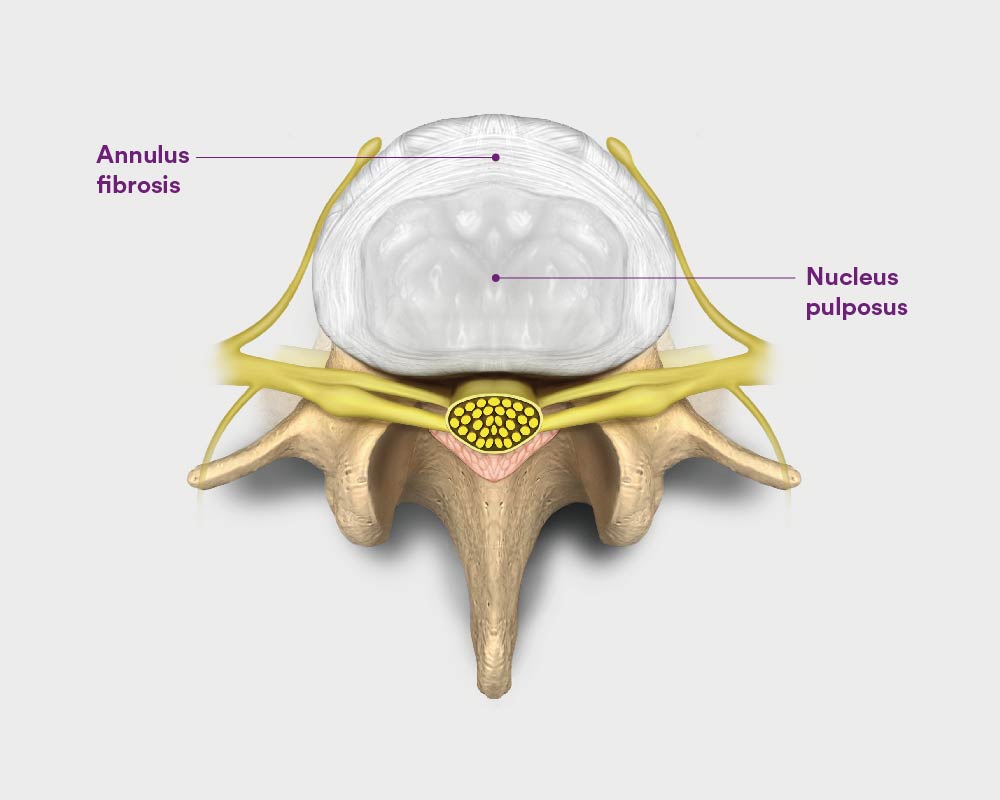

Pure Health - Anatomy 101 - Supraspinous ligament and interspinous ligament 📚 The supraspinous ligament and interspinous ligament work together to limit flexion of the spine by limiting separation of the spinous

DOCS - The interspinous ligament is located between the spinous processes of adjacent vertebrae in the spine. It extends from the base of one spinous process to the apex of the next,